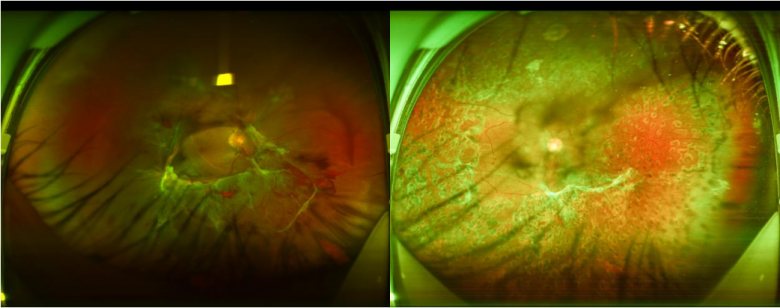

36岁的温先生,身材肥胖,日常酷爱甜食、油腻的食物。近日,温先生右眼视力视力忽然骤降,”接诊时,我们初步怀疑是视网膜脱落,经过系统检查后,发现他更像是糖尿病视网膜病变。”佛山爱尔眼科医院总院眼底病科主任赵抒羽说。经眼底荧光血管造影、血糖、糖化血糖蛋白检查后发现,温先生由于血糖升高,高血糖影响造成了眼底视网膜血管损害,需经手术治疗来降低失明的发生率。医生建议其先到综合医院降血糖,调整到正常数值后再回来安排手术。

左图为右眼术前情况,右图为右眼术前情况